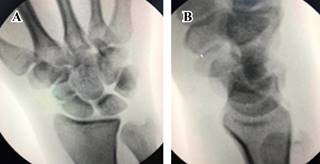

Una hora después de su ingreso, bajo previo consentimiento del paciente, en un primer tiempo se realiza reducción cerrada de la luxación del carpo mediante la maniobra de Tavernier con control fluoroscópico y bajo anestesia general, logrando adecuada reducción de la luxación. (Figura 3) Posteriormente se coloca una férula tipo pinza de azúcar y se decide programar en un segundo tiempo la reducción y osteosíntesis del escafoides debido al importante edema en dicha mano.

Figura 3: Imagen fluoroscópica (A) anteroposterior y (B) lateral de muñeca, en la cual se muestra adecuada reducción de luxación de los huesos del carpo.